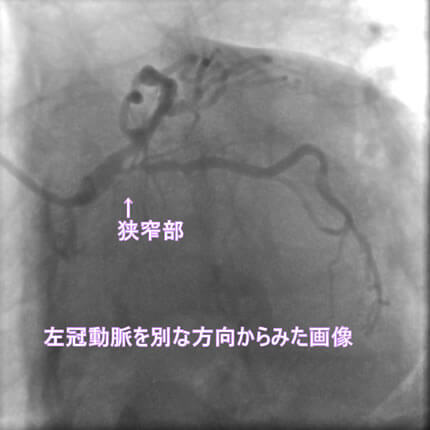

1番目の患者さんは80歳の男性です。この方の危険因子は高血圧、高脂血症、喫煙です。この方の冠動脈造影と腹部CT画像を示します。図1-1から1-8の画像は全て全てこの患者さんの画像です。

図1-3 左冠動脈造影像

よく解らないと思いますが、冠動脈に多数の狭窄があることと冠動脈が「こぶ状変化(医学用語で瘤状変化)」を生じているのが解ると思います。